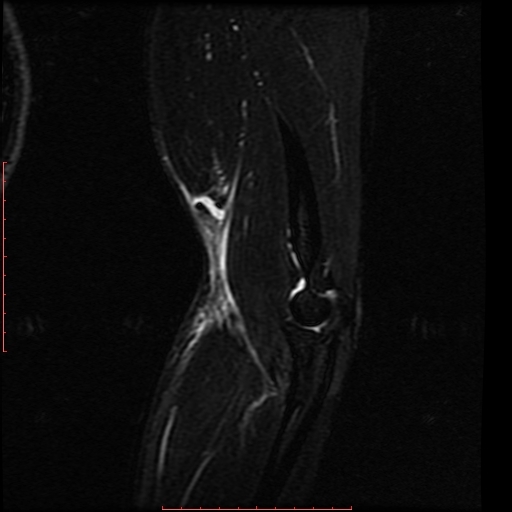

Anamnese: Ellenbogenschmerzen nach Gewichtheben. Welche Pathologie können Sie auf dem vorliegenden MRT des Ellenbogens erkennen?